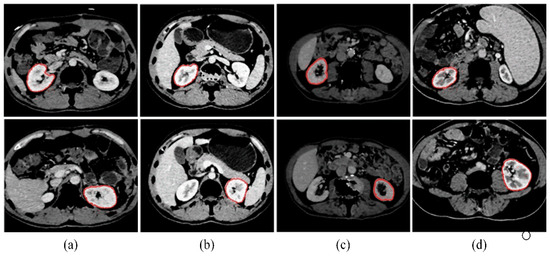

The kidney is surrounded by various tissues and organs, such as the spleen, muscle, spine, blood vessels, and others, and its grayscale is similar to that of the surrounding tissue. Figure 12a–d displays the results of three consecutive slices from four different sequences, respectively. The red curve represents the segmentation contour of the kidney. Despite the challenges posed by the adjacent tissues and organs, our kidney segmentation method is able to achieve desirable results. Moreover, it is reasonable to begin with the initial slice and proceed to segment all the slices in a volume in sequence.

To demonstrate the high performance of our kidney segmentation framework, we compare our proposed method with the multi-atlas [35] and kernel graph cuts (KGCs) [36]. For the KGC experiment, the K-Means cluster result is utilized to construct the graph and perform the postprocessing of the filling operation to achieve the best possible results. Figure 14 depicts the kidney segmentation results of four kidneys, where the three rows indicate the corresponding segmentation results of the multi-atlas method, the KGC method, and the proposed method, respectively. The manual ground truth is shown in green, while the segmentation result is in red. From Figure 14a, it can be observed that the multi-atlas method fails to segment the right kidney and the right kidney is over-segmented. The KGC method, as seen from the results, has over- or under-segmentation problems. Additionally, it could not handle low-contrast images, as demonstrated in Figure 14f, and the intensity inhomogeneity of kidneys, particularly the renal medulla, which is not surrounded by the cortex (see Figure 14g). For kidneys with tumors, the multi-atlas method fails to segment the entire kidney, as shown in Figure 14d, and the KGC method cannot segment the tumor part, as shown in Figure 14h. In comparison, our method accurately segments not only the healthy kidneys but also the tumors, as shown in Figure 14l. In comparison with the multi-atlas method and the KGC model, our proposed approach could segment kidneys accurately.

Figure 12. (ad) Results of three consecutive slices from four sequences, respectively. The red curve represents the segmentation contour of the kidney.

Figure 14. Comparative segmentation results of four randomly chosen CT slices for the multi-atlas [34] (ad), the KGC [35] (eh), and the proposed approach (il). The segmentation result is shown in red, while the manual ground truth is shown in green.